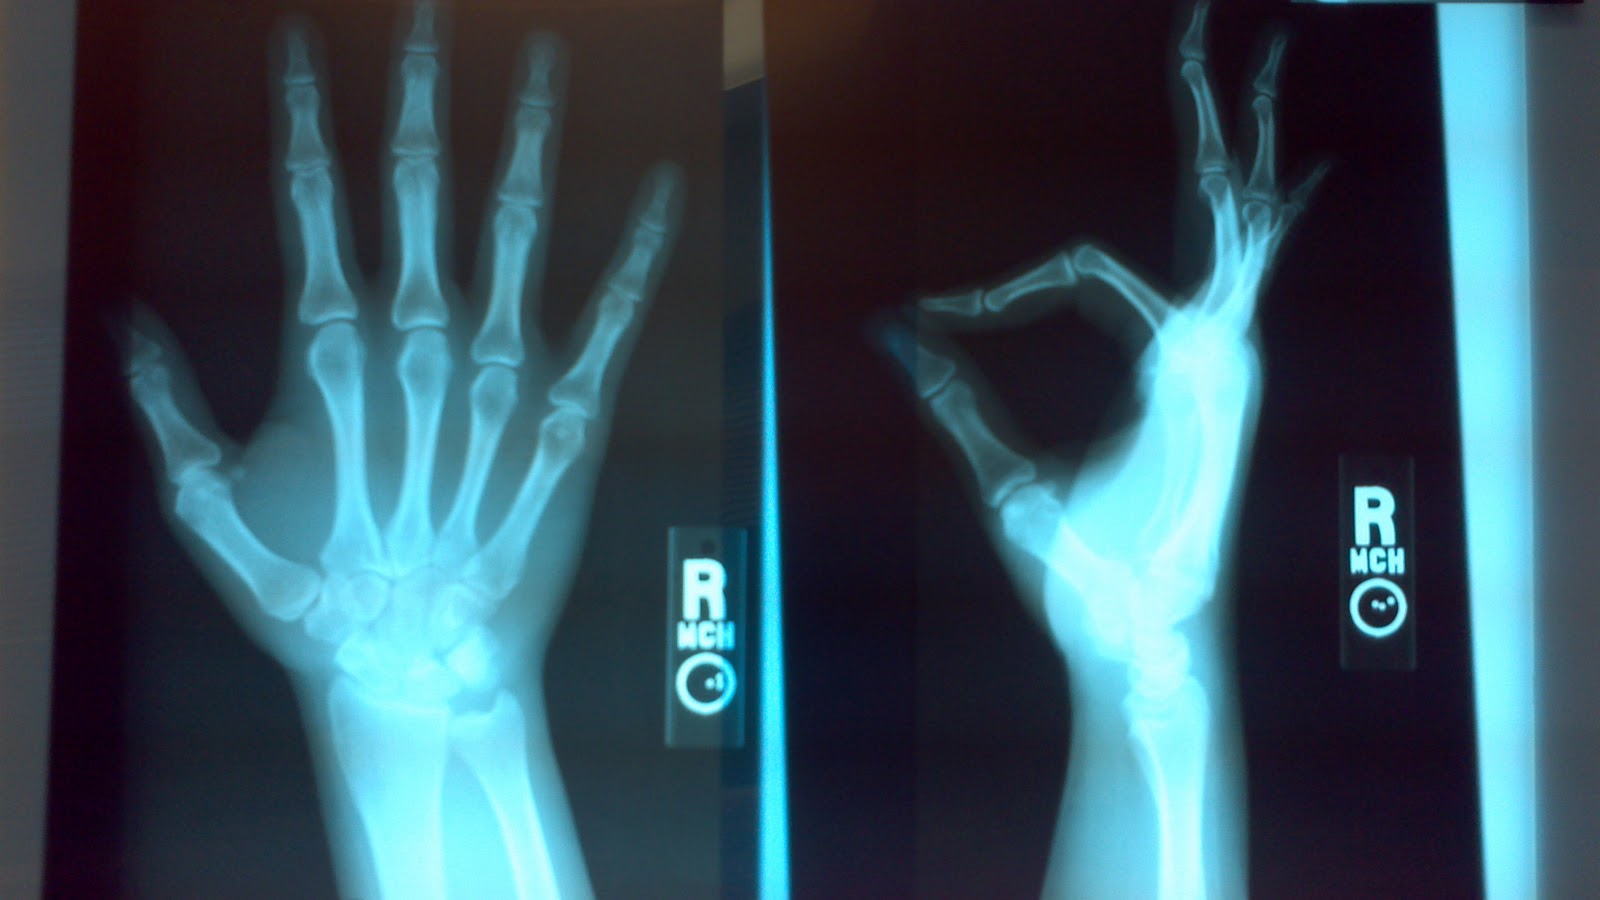

| Never leave me alone in the examanation room...especially with my x-rays ;) |

I think I have mentioned a time or two lately that I have been seeing some doctors :) Anyway, when I went in for my physical last week, I mentioned to my doctor that I had a "lump" on the inside of my middle finger, where it meets my palm. It has been there about 6 months and started out the size of the tip of my pen, and now it is pea sized and hurts when I bump it. He looked at it and said I needed to see an Orthopedic doctor who specialized in hands, and that is most likely needs to come out.

I saw the hand doctor today. He agreed, the cyst needs to come out. It's perfectly harmless in itself, but it's growing, and will eventually cause more pain and could cut off circulation, or pinch a nerve. It will be a simple outpatient surgery next Tuesday. They will sedate me and give me a local anaesthetic. I'll be off of work for the day (woot! Sleep! Drugs! No chores! (yeah right...) ). However, anytime people are going to cut into you there is risk..so, prayers are always welcome :)